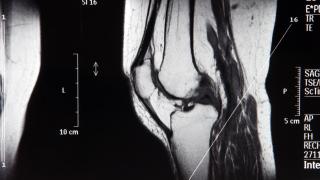

En este caso, probaron esta hipótesis en 68 hombres y mujeres diagnosticados de osteoartritis de rodilla leve o moderada, y posteriormente usaron exploraciones de resonancia magnética avanzadas para controlar si la intervención había tenido éxito.